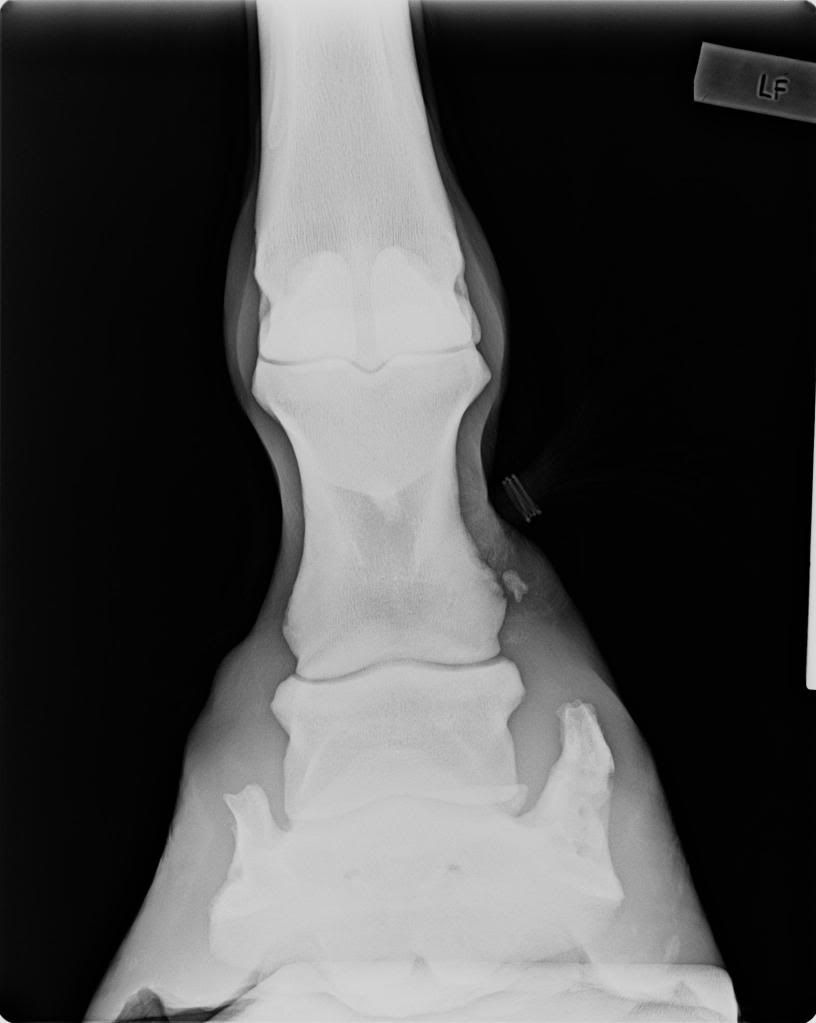

Horse Sidebone X Ray . Can my horse be treated for sidebone? sidebone is hardening of the cartilages on either side of the coffin bone in a horse's hoof. The grades are as follows: Experts aren't sure why these usually springy. There are several methods for grading sidebone lesions, however most literature uses the grading system proposed by ruohoniemi et al. How will i know if my horse has sidebone? despite their similar names and presentations as firm swellings in the pastern region, sidebone and ringbone describe two different and unrelated processes occurring within the horse’s digit. Whilst the sidebone is developing. How can i prevent my horse from developing sidebone?

Horse Sidebone X Ray sidebone is hardening of the cartilages on either side of the coffin bone in a horse's hoof. sidebone is hardening of the cartilages on either side of the coffin bone in a horse's hoof. Can my horse be treated for sidebone? How can i prevent my horse from developing sidebone? How will i know if my horse has sidebone? The grades are as follows: There are several methods for grading sidebone lesions, however most literature uses the grading system proposed by ruohoniemi et al. Whilst the sidebone is developing. despite their similar names and presentations as firm swellings in the pastern region, sidebone and ringbone describe two different and unrelated processes occurring within the horse’s digit. Experts aren't sure why these usually springy.

Radiography, Xray, Fetlock or Pastern Horse Side Vet Guide Horse Sidebone X Ray despite their similar names and presentations as firm swellings in the pastern region, sidebone and ringbone describe two different and unrelated processes occurring within the horse’s digit. Whilst the sidebone is developing. Experts aren't sure why these usually springy. There are several methods for grading sidebone lesions, however most literature uses the grading system proposed by ruohoniemi et al.. Horse Sidebone X Ray.

Radiography, Xray, Foot Horse Side Vet Guide Horse Sidebone X Ray The grades are as follows: sidebone is hardening of the cartilages on either side of the coffin bone in a horse's hoof. There are several methods for grading sidebone lesions, however most literature uses the grading system proposed by ruohoniemi et al. How will i know if my horse has sidebone? How can i prevent my horse from developing. Horse Sidebone X Ray.